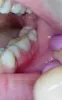

В последнее время, примерно 2 недели, очень сильно стали кровоточить дёсны при чистке зубов. Раньше такое наблюдалось, но не так сильно.

Вчера вечером появился дискомфорт при приёме пищи, было больно пережёвывать. Сегодня утром обнаружила язвы на дёснах. Не могу нормально есть и пить, болезненные и неприятные ощущения. Никаких других симптомов нет (повышенная температура и пр.). Несколько лет назад у меня был стоматит.

Это может быть стоматит? Что предпринять? Чем лечить?